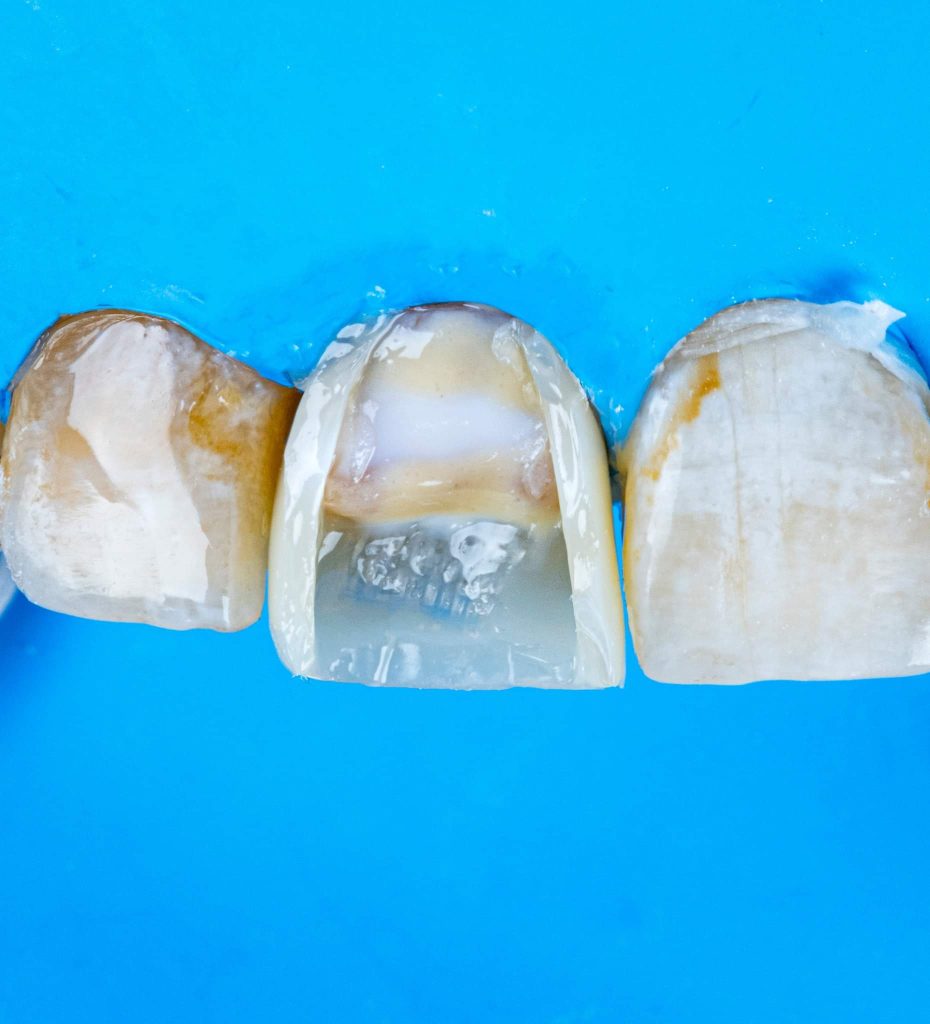

1.Masking the discoloration: This is where one or several shades of composite resin are used to camouflage the underlying darkened tooth shade. For severe discolorations, a resin-based opaque layer placed over the discolored areas of tooth may be required. This is then covered with dentine and enamel shades to match the adjacent teeth.

This is a case of discolored right central incisor for a 21 years-old-male patient. He had a history of previous trauma 2 years ago to his tooth and fracture, that was managed with a composite restoration. After clinical examination and x-ray imaging, the tooth was non-vital with periapical lesion.

After discussing the treatment options with the patient, he chose the direct composite veneer. The treatment included endodontic treatment, internal bleaching, direct composite veneer for the right central, and aesthetic reshaping for the laterals and left incisor also by composite restoration. The case completed in 2 sessions.